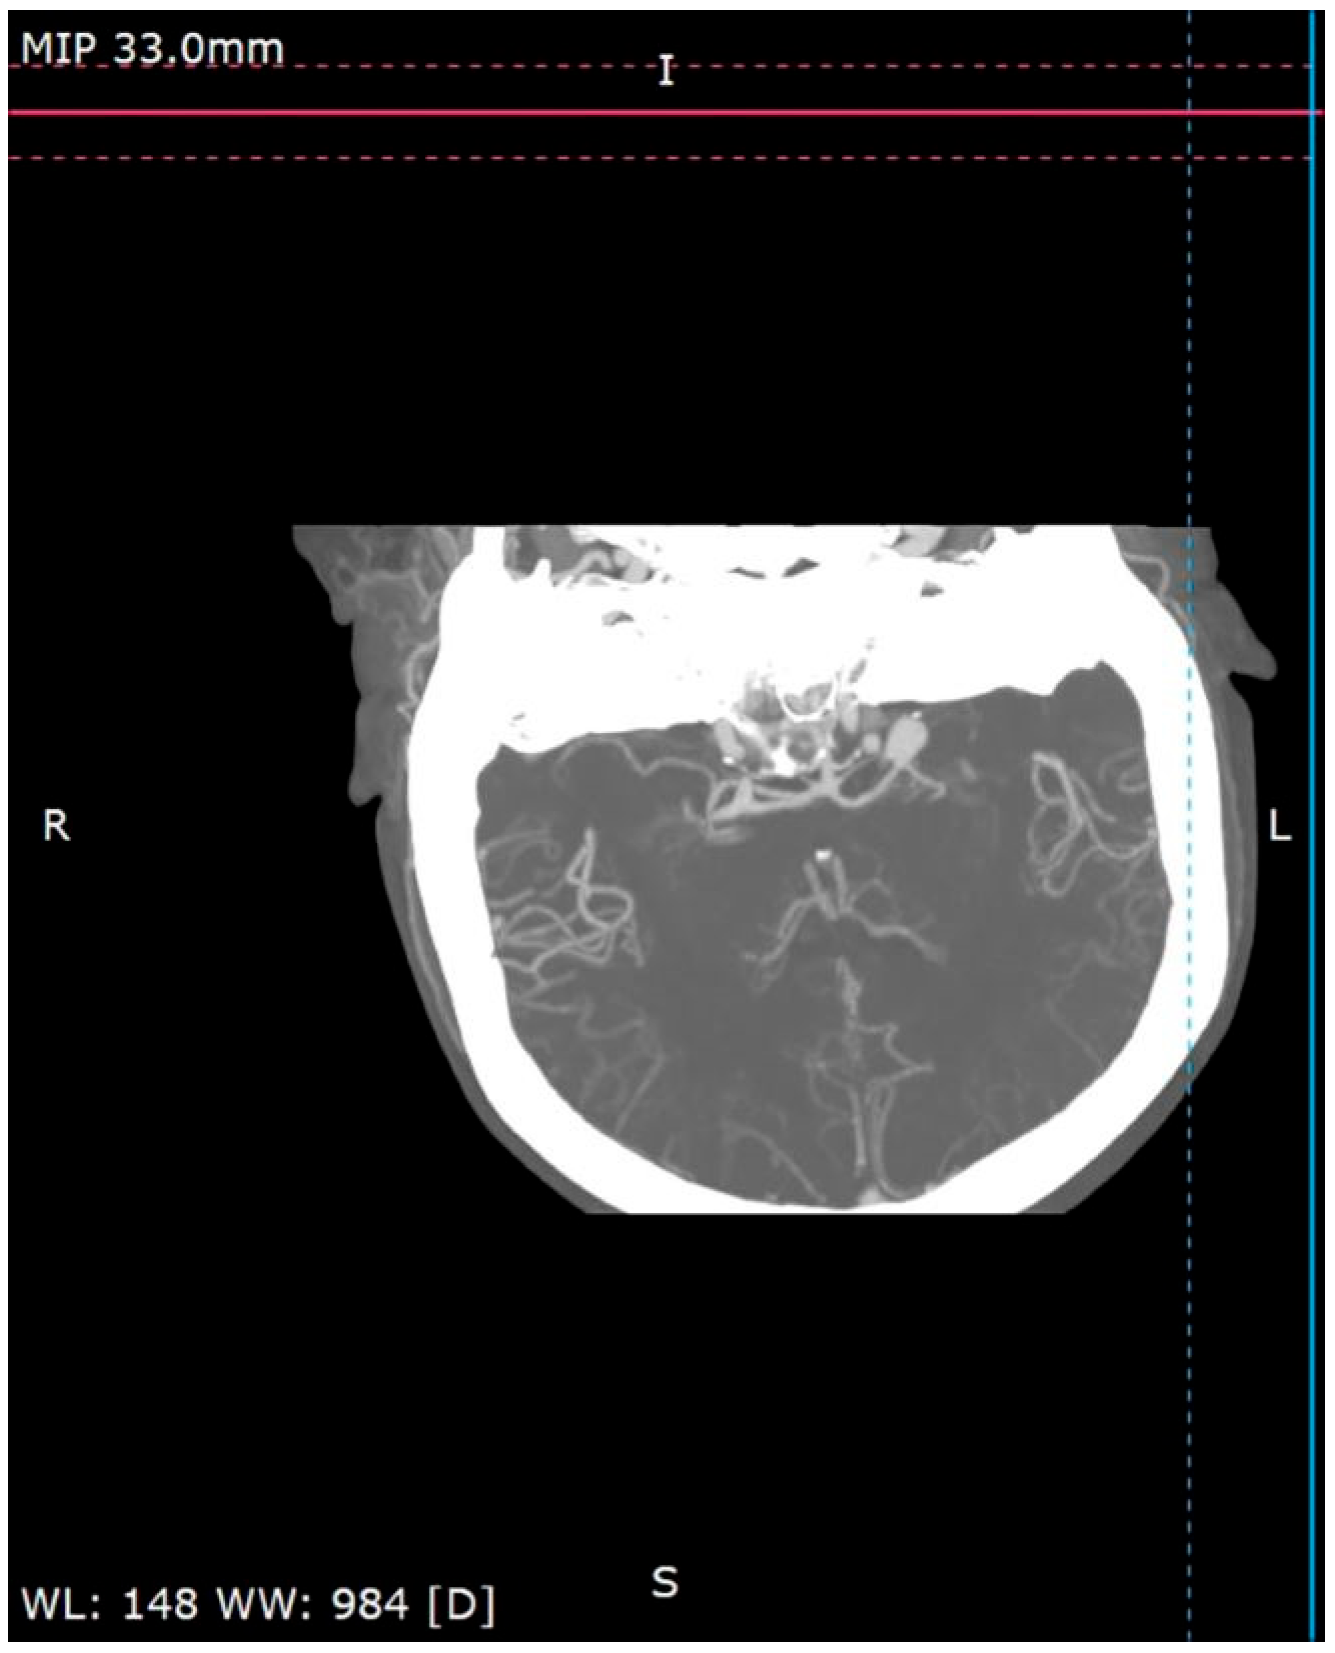

A 58-year-old woman treated for exudative pericarditis (effusion up to 6 mm) for the last 6 months was referred to a hepatologist/infectious diseases specialist with hypoechoic unclear lesions in the liver due to suspected hepatic tumor. Computed tomography confirmed simple hepatic cysts, while blood analysis revealed significant eosinophilia (23.4% in percentage, normal range 1–6%; eosinophil count: 1.45 in thousand eosinophils per microliter (K/μL), normal range 0.02–0.5 K/μL). The patient denied any symptoms, such as fever, abdominal pain, weight loss, cough or diarrhea in recent months; however, she described left-sided subjective eyeball enlargement, pain and redness. Her history included travels to Mexico, Egypt and Tunisia, as well as occasional raw meat consumption in Poland. She also had a dog, which did not receive regular parasite screenings and preventive medications. Her father had died from liver cancer. Lab tests confirmed the presence of IgG antibodies against Toxocara canis and sustained eosinophilia (18.1% in percentage, normal range 1–6%; eosinophil count: 1.01 in thousand eosinophils per microliter (K/μL), normal range 0.04–0.4 K/μL). Echinococcosis was excluded based on negative serology. Diagnosis of toxocariasis was further supported by clinical manifestations and exposure history with positive serology, and the patient was treated with mebendazole (200 mg twice a day for 5 days). Due to the suspicion of an ocular parasitic invasion, she was sent for an ophthalmological consultation. The ophthalmological examination was inconclusive, but head MRI revealed vascular abnormalities in brain arteries. CT angiography confirmed four aneurysms with one causing the constriction of an artery supplying the left eyeball (Figure 1, Figure 2 and Figure 3): two cerebral aneurysms of LICA (left internal carotid artery) size: 4.2 × 8.7 × 3.5 mm and 9.8 × 7.8 × 10.7 mm, one cerebral aneurysm of LMCA (left middle cerebral artery) size: 3.5 × 3.3 × 3.2 mm and the fourth enlargement for differentiation between an aneurysm and an infundibular dilations (3 mm) of LMCA. Clipping the aneurysms dissolved the ophthalmological problems. During the last check-up, normalization of the eosinophil count, full resolution of the ocular symptoms and no pericardial effusion were seen, further supporting our diagnosis of visceral toxocariasis. Hepatic cysts began to disappear. The patient was recommended to perform an abdominal ultrasound every 6 months.

Figure 2.

Cerebral 3D CT angiography.